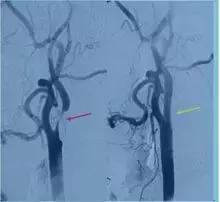

脑动脉狭窄(下图),急性或慢性脑动脉闭塞,颅内静脉窦血栓等。